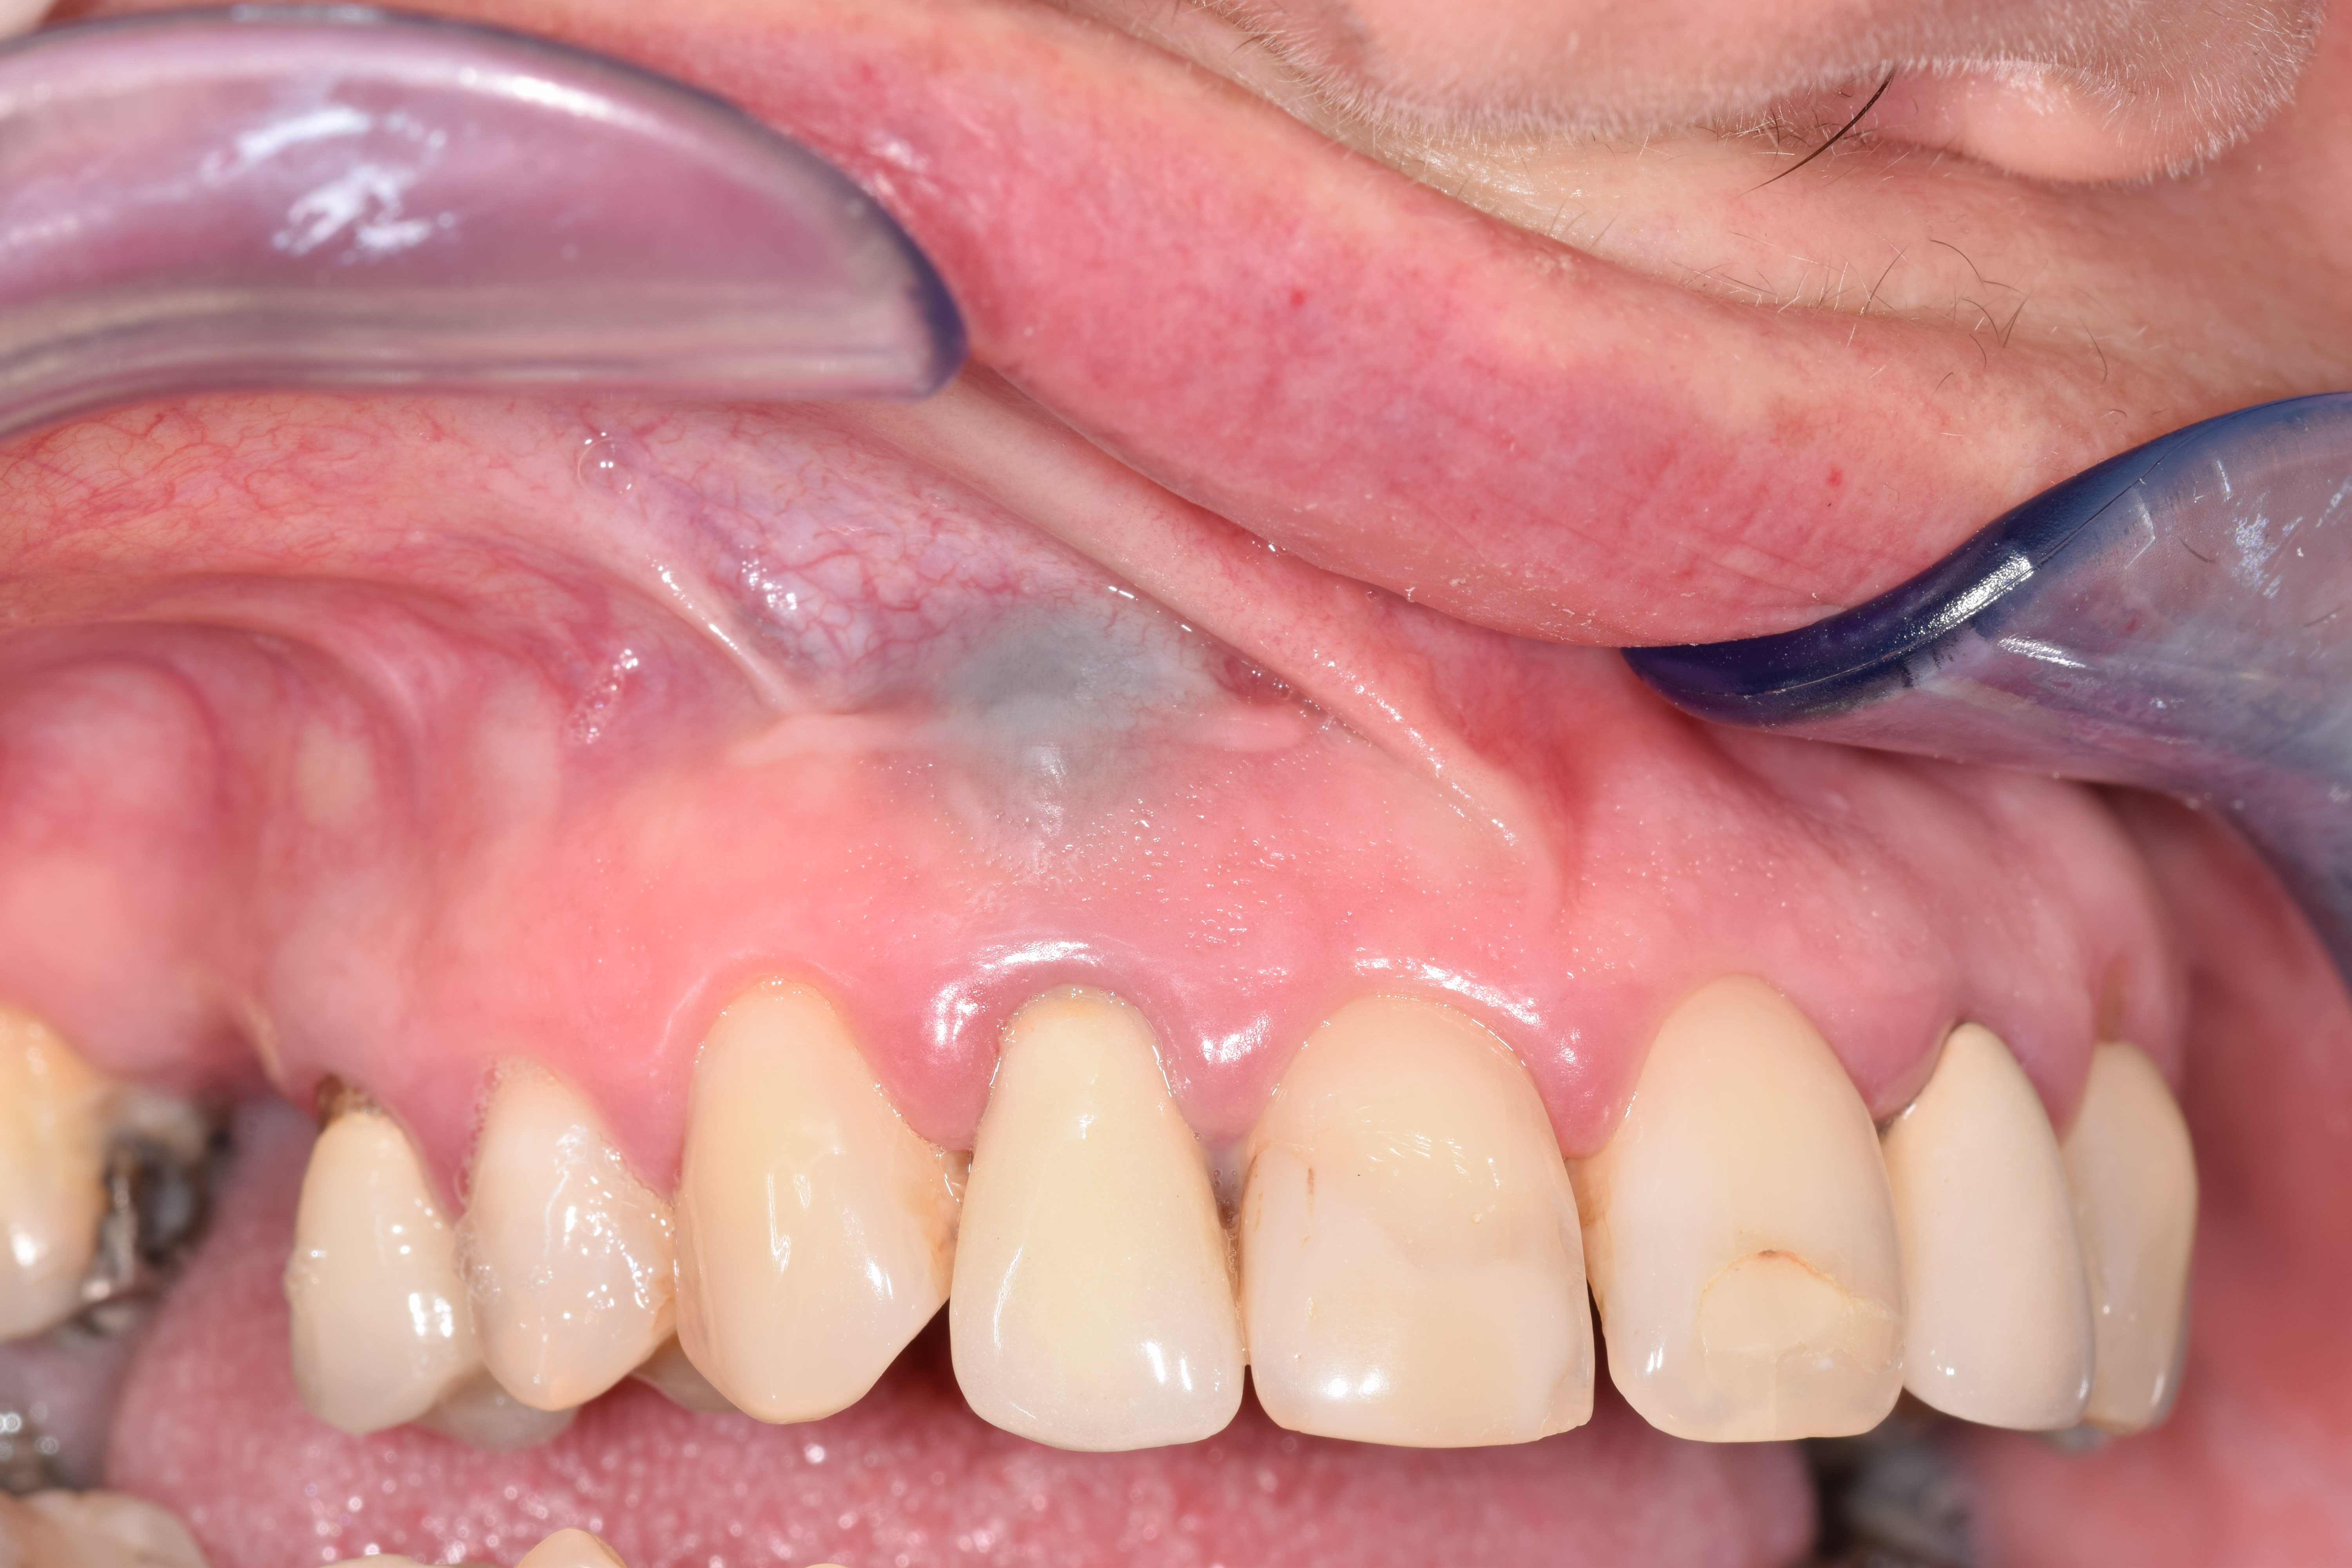

la 12, traitée endo, avec une couronne à adaptation correcte, dont l’esthétique convient à la patiente. 1 résection apicale faite il y a qqs années avec obtu à l'amalgame. une lésion kystique de env 1cm de grand axe s'est installée depuis au moins un an. Au cbct : lesion centrée sur l'apex, avec une fenestration vesibulaire, ne s'etendant pas jusqu'en palatin. (malheureusement j'ai pas acceès aux rx en ce moment, seulement une photo pre op...)

le kyste comprenait une enveloppe et contenu liquide, adhérant à la muqueuse vesitibulaire. J'ai tres bien cureté les tissus osseux et degranulé en vestibulire autant que possible mais j'avais peur de ne pas avoir de quoi recouvrir l'os si je virais toute la muqueuse ou l'adhesion du kyste se faisait.